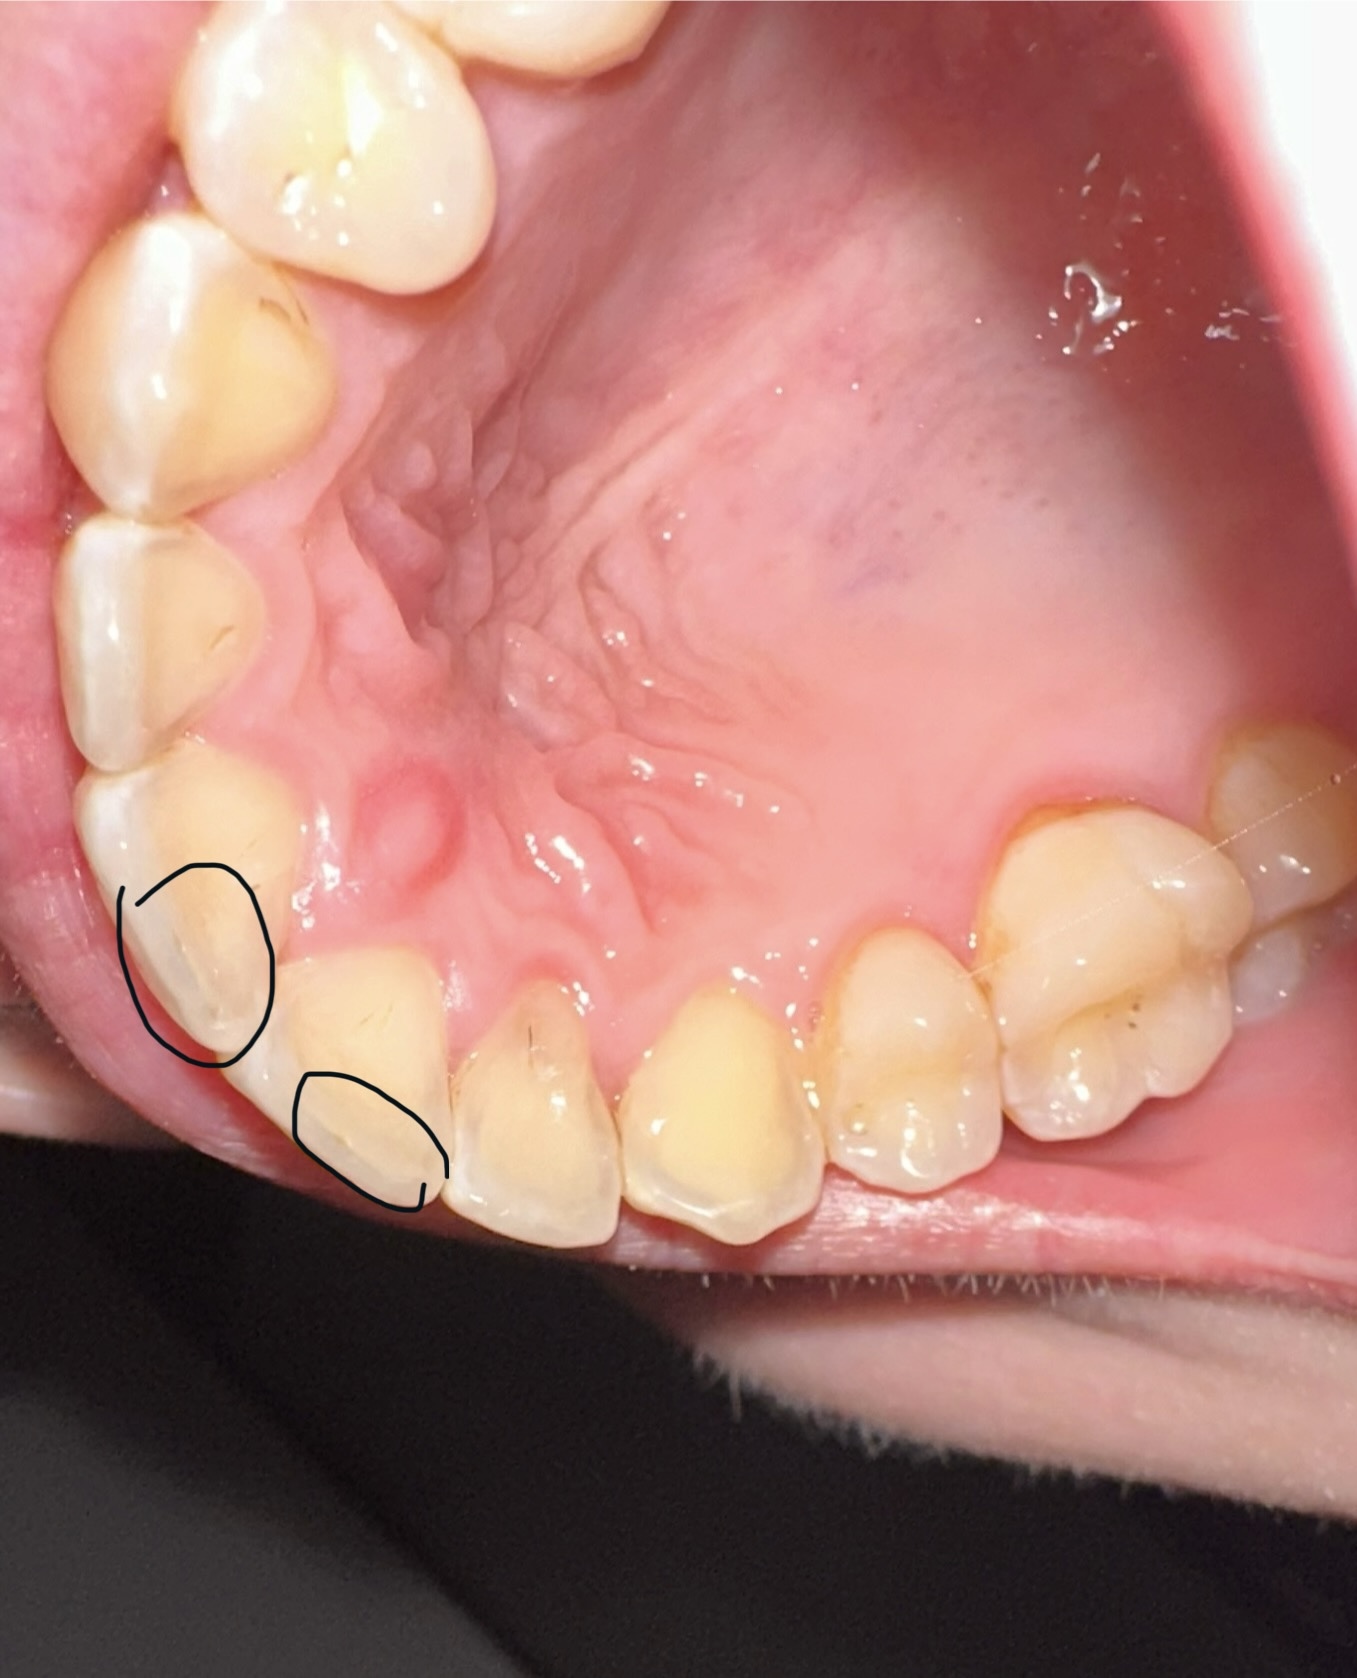

Ist das eine Zahnerosion zu sehen und was sind die eingekreisten Stellen?

ja leichte zahnerosion, muss man nichts machen …

Und was sind die eingekreisten Stellen?

zahnerosion …